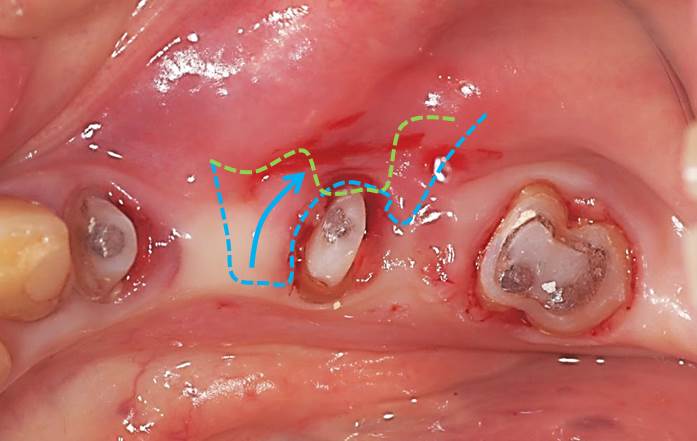

そこで、下写真のように青線部分の「動かない歯茎」を、緑線部分へ移動して歯の周囲(頬側)に「動かない歯茎」を形成する計画としました。